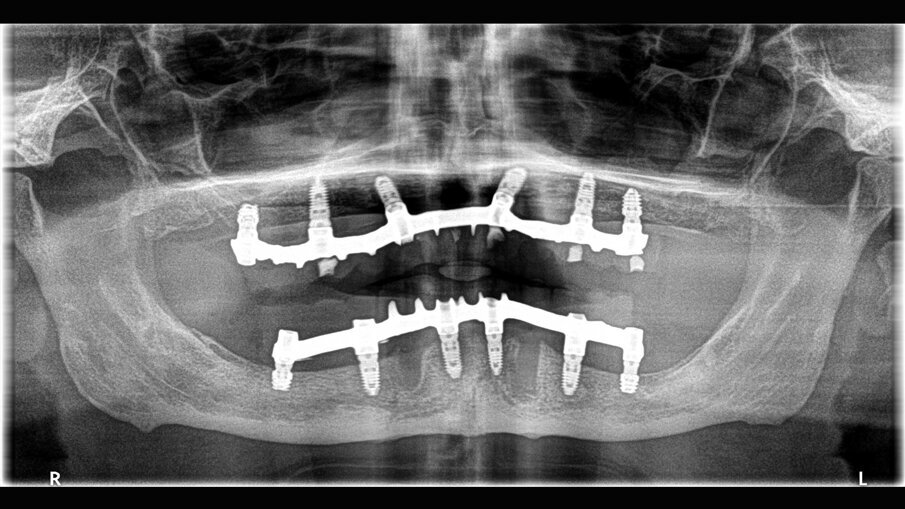

Il paziente si presentò alla nostra osservazione lamentando una diminuzione della capacità masticatoria. All’osservazione clinica e radiografica (Figg. 1, 2) si evidenziava la mancanza di numerosi elementi dentari e di una diffusa malattia parodontale, il tutto complicato dalla presenza di carie destruenti su tutti gli elementi dentari con migrazione degli stessi. Lo spostamento dei denti aveva portato a perdita della dimensione verticale e di tutti i punti di riferimento per la ricostruzione della dentatura.

Al paziente fu spiegato che la strategia migliore consisteva nell’estrazione di tutti gli elementi dentari e l’inserimento di sei impianti in ogni arcata dentaria e successivamente il ripristino delle arcate con due protesi tipo Toronto. Si decise di non estrarre subito i quattro canini perché sarebbero serviti per stabilizzare le mascherine chirurgiche durante la chirurgia. Lo studio del caso e la sua realizzazione fu fatta con metodo analogico. Due modelli in gesso furono montati alla giusta dimensione verticale e fu realizzato il montaggio dei denti per visualizzare il risultato finale (Fig. 3). Dal montaggio dei denti furono realizzate le mascherine chirurgiche che sarebbero state utilizzate per gli esami radiografici tridimensionali e avrebbero guidato il posizionamento degli impianti durante la chirurgia. All’esame radiografico tridimensionale (Figg. 4-7) si notava la presenza di una quantità esigua di osso coronalmente ai seni mascellari e al nervo alveolare inferiore. Si decise di inserire impianti extracorti 4,5 mm di lunghezza in queste zone, per evitare sia impianti inclinati sia cantilever molto estesi. Lo studio della scala dei grigi, o scala Hounsfield, mostrava una densità ossea tale da consentire il carico immediato anche in queste zone. Ovviamente sarebbe stata necessaria la conferma intra-operatoria valutando clinicamente la compattezza dell’osso tramite la fresatura.